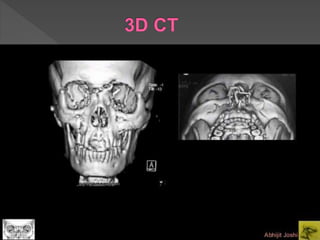

 A 3D CT, as shown, can help assessing

usually made intraoperatively.

 This 3D CT shows a bilateral NOE type II

with involvement of the nasal bones.

 Be aware that a 3D CT often

underestimates the severity of the injury.